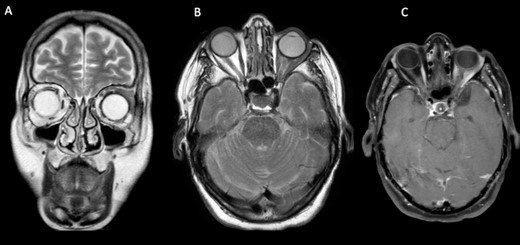

MRI scan showed a lump involving the left superior and lateral extraocular rectus muscles, with slight enhancement along with infiltration of surrounding fat tissue between the ophthalmic nerve and lateral rectus muscle (Fig. 2).

Cerebral and orbital MRI. (A–B) Coronal and axial T2-weighted MRI show iso-intense thickening of the left lateral and superior rectal muscles with fat atrophy. (C) Axial T1-weighted MRI with gadolinium enhancement and fat suppression reveals slight enhancement of the left lateral and superior rectal muscles with infiltration of the surrounding tissues.